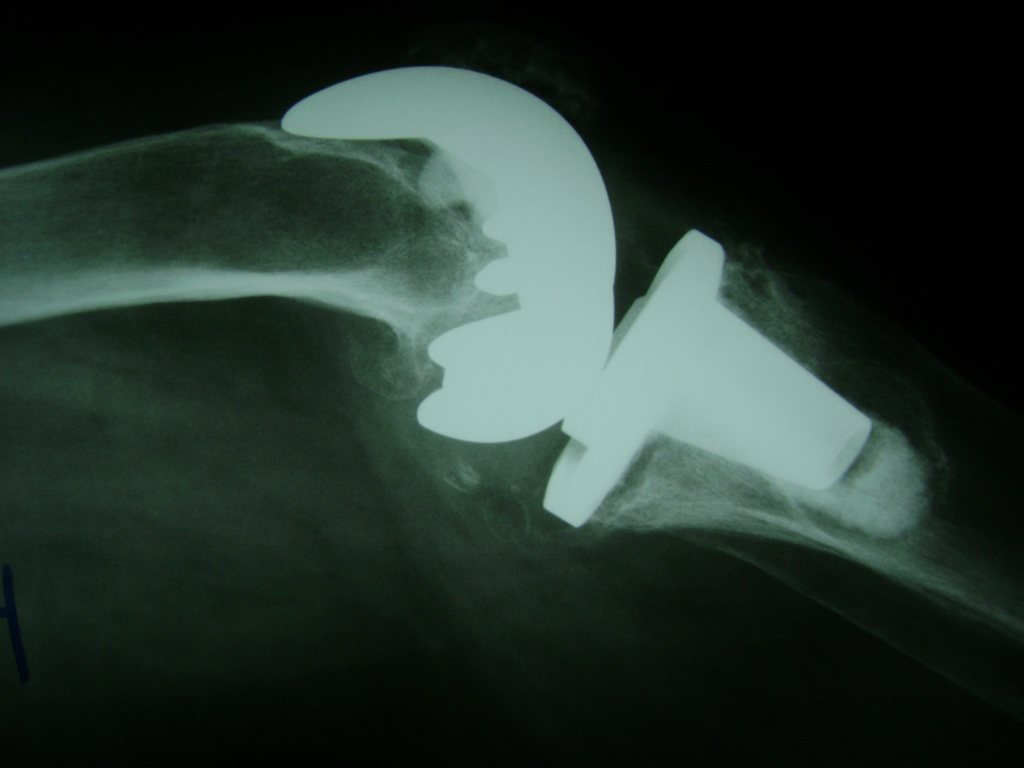

Cirugías de Codos - Rodilla

La artroscopia de rodilla es un cirugía en el cual la estructura interna de la articulación es examinada ya sea para realizar un diagnostico o para realizar un tratamiento, este procedimiento se realiza utilizando un instrumento parecido a un pequeño tubo llamado artroscopio.